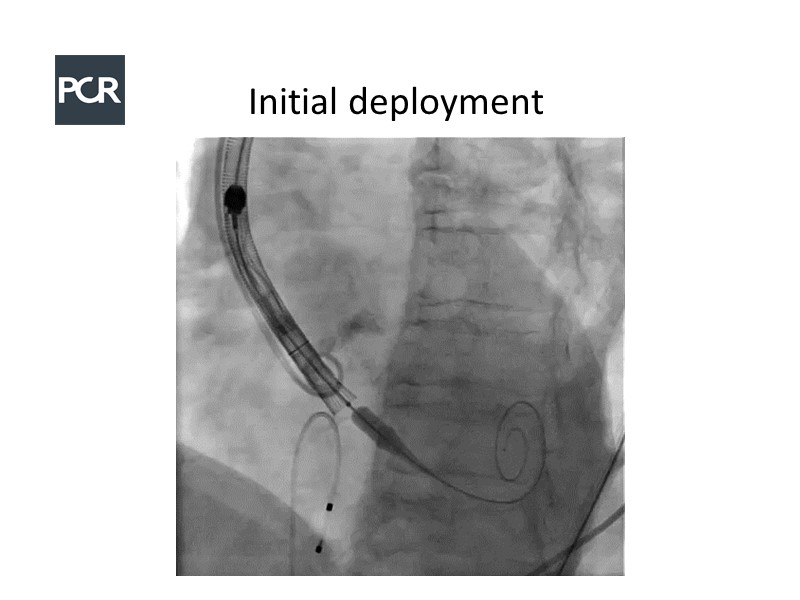

In this session, a panel of experts introduce the VitaFlow TAVI system, a good option for patients with complex anatomies. They also present the five-year results of VitaFlow in severe aortic stenosis.

- To learn about the VitaFlow TAVI system and the five-year results of VitaFlow in severe aortic stenosis